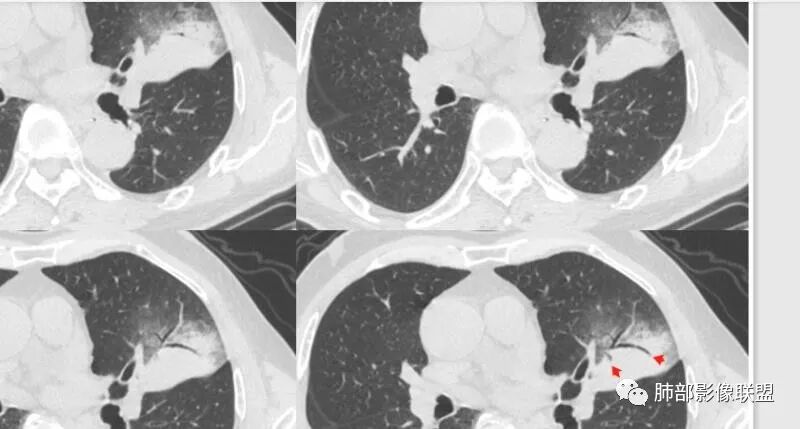

大雄:

这三个月后的

发了后面这个,就不用纠结了,直接秒了。

我只是要告诉大家,不是二元,就是肿瘤,没有什么感染,磨玻璃都没消失。

低分化腺癌坏死常见,转移的淋巴结坏死也常见,这个奇怪的就是淋巴结没有转移,如果有淋巴结肿大,应该会更容易想到低分化腺癌。

周围磨玻璃影是飘出去的粘液,也是肿瘤的一部分吧?

尘缘:

@小赵 这个不一定是粘液,很可能还是周围癌性浸润。看术前复查,原磨玻璃区呈明显小叶间隔增厚改变了。说明还是癌性淋巴浸润。

@温附一影像科,傅钢泽 应该是STA(气腔播散)加癌性淋巴管炎。

支气管稍扩张→有张力,GG0边缘清楚,局部有小叶间隔阻挡。

反思,恶性膨隆,远端空洞,强化坏死不均,里面血管似乎也是增粗,边界不清,似乎有侵犯。坏死还是边界不清。

1、团片状,实行密度区外观整体圆顿,位于上叶尖后段与下舌段区间。局部膨隆,但未见分叶,肿瘤多见。

2、偏心空腔病灶,气腔略呈新月形,壁不规则,腔内结节相对密实,明显强化且不均,支持新生物而非曲菌球等。炎性空洞多有强化环。

3、病变强化较明显,其内隐约显示多发小斑片状无强化灶,可疑边界不清小灶坏死区。病灶内血管影浅淡、模糊不规则。

4、支气管改变:上舌段支气管远段延入部分稍示僵硬。尖后段见分支支气管阻塞,恶性多见。

5、周围磨玻璃,3个月后逐渐转为密实,应符合当初附壁生长为主,且逐渐向实体成分转换。

6、病变长轴平行且受限于胸膜,外围大内带小,符合外朝内发展病变。“腔内结节状明显强化”加之支气管改变有力支持新生物诊断。如此大范围边界不清的磨玻璃影让人浮想联翩。如此大范围病灶,肺门纵隔未见肿大淋巴结也让人意外。